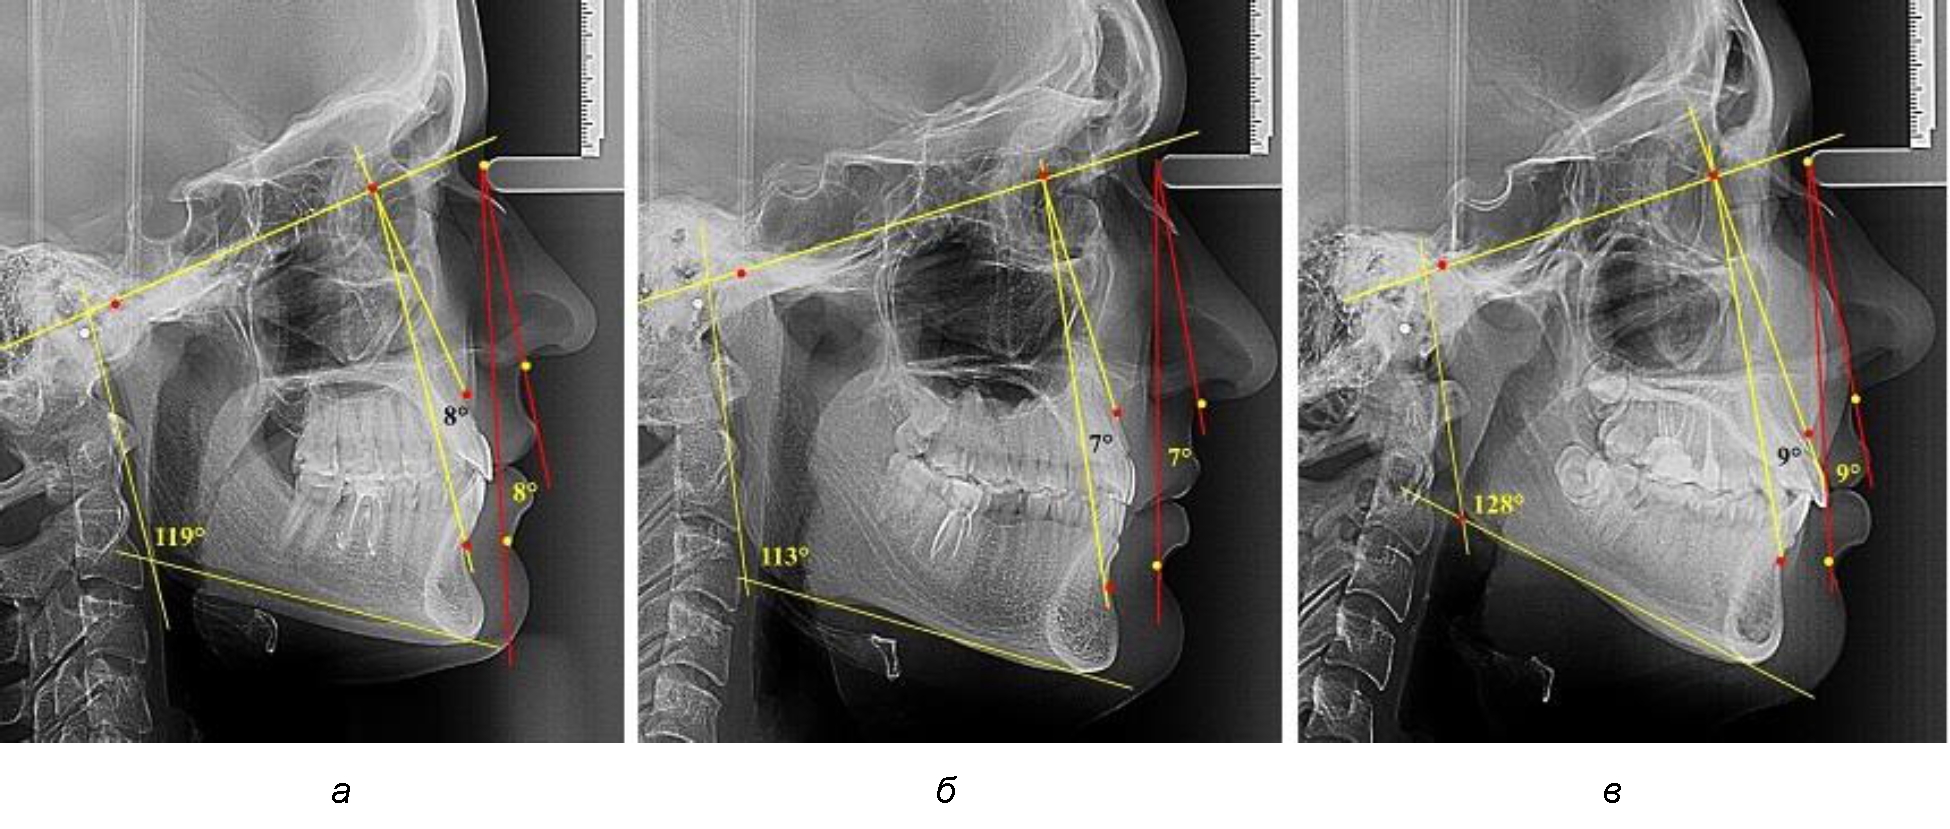

В группе людей с нейтральным типом нижнечелюстного угла величина лицевого межгнатического угла составляла (7,98 ± 0,49)° при использовании как кожных, так и костных ориентиров (рис. 3).

Рис. 3. Параметры кожного и костного лицевого межгнатического угла при нейтральном (а), горизонтальном (б) и вертикальном в типах угла нижней челюсти

В группе людей с горизонтальным типом нижнечелюстного угла величина лицевого межгнатического угла была несколько меньше и составляла (7,05 ± 0,37)° при использовании как кожных, так и костных ориентиров.

В группе людей с вертикальным типом нижнечелюстного угла величина лицевого межгнатического угла была больше, чем при других типах и составляла (9,23 ± 0,45)° при использовании как кожных, так и костных ориентиров. Таким образом, при всех типах нижнечелюстного угла отмечалось равенство параметров лицевого межгнатического угла как по кожным, так и по костным ориентирам. Полученные сведения легли в основу определения лицевого межгнатического угла на фотографиях в профиль при различных позиционных типах лица.

В группе людей при нормопозиции челюстей величина лицевого межгнатического угла была несколько меньше и составляла (8,12 ± 0,41)°. При антепозиции величина угла была несколько меньше и составляла (7,0 ± 0,52)°.

В группе людей с ретропозицей величина лицевого межгнатического угла была больше, чем при других типах и составляла (8,25 ± 0,43)°. Достоверных различий не отмечено, что позволяет величину лицевого угла от 6 до 10° рассматривать как оптимальные показатели для физиологического расположения нижней челюсти по отношению к положению верхней челюсти.

При оценке параметров лицевого межгнатического угла при аномалиях окклюзии учитывали патологии, классифицированные Энглем. При аномалиях окклюзии I класса величина исследуемого угла была близка к показателям, полученным у людей с физиологической нормой окклюзионных соотношений, что свидетельствует о зубоальвеолярной форме патологии и оптимальном расположении челюстей в структуре лицевого комплекса (рис. 5).

Рис. 5. Параметры лицевого межгнатического угла при аномалиях окклюзии I класса (а), II класса (б) и III класса (в)

Для аномалий окклюзии II класса Энгля было характерно увеличение угла более 11°, и оно зависело от степени дистального смещения нижней челюсти.

Для аномалий окклюзии III класса характерно уменьшение угла менее 5° вплоть до отрицательных значений.